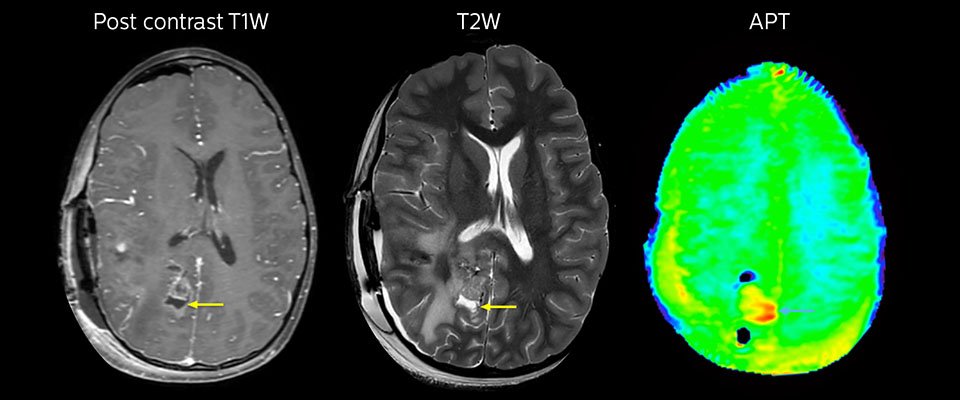

Große metastatische Hirnläsion

Diese 10-jährige Patientin unterzog sich vor 7 Jahren der Resektion eines Ewing-Sarkoms, doch jetzt wurde eine große metastatische Läsion im Gehirn entdeckt. Diese Läsion zeigt deutlich ein erhöhtes APT-Signal.

MRT mit APT nach der Resektion

Unmittelbar nach der Resektion wurde erneut eine MRT durchgeführt. Die T2-gewichteten und kontrastverstärkten T1-gewichteten Bilder lassen keine eindeutige Unterscheidung von Residualtumorgewebe und postoperativen Gewebeveränderungen zu. Auf dem APT-Bild ist noch ein hohes Signal zu sehen, das auf Residualtumorgewebe hindeuten würde.